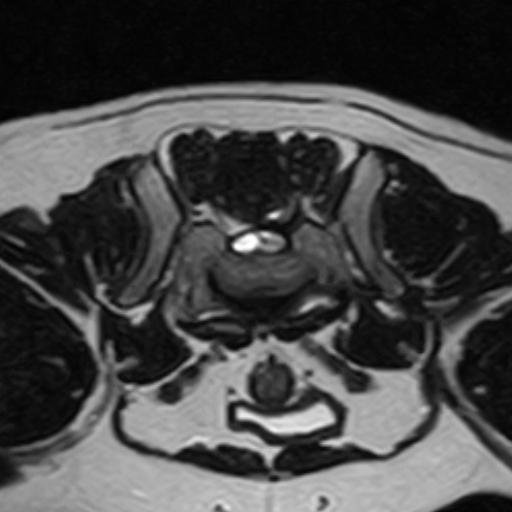

A section of the spinal cord is known as the cauda equina. It gets its name from the nine nerves that make up its structure (cauda = tail; equina = horse). The cauda equina is located at the base of the spinal cord (the tail of the spine). In addition to controlling the movement of the back legs and the tail, it also maintains urinary and faecal continence.

The spinal cord itself runs through a bony tunnel or channel within the vertebrae of the back. The bones surround and protect the delicate nervous system. Within the spine, the individual vertebral bones are interconnected and allow great flexibility between areas, e.g. neck, lower back. A mobile and flexible spine and a healthy spinal cord are essential for normal function.

In cauda equina syndrome, nerves of the cauda equina become compressed or trapped. Pain and paralysis caused by nerve compression are common signs, along with faecal and/or urinary incontinence, and lameness of the pelvic limbs (similar to sciatica in people). Degenerative lumbosacral stenosis is the most common disease causing problems (see factsheet). The vertebrae in the spine (vertebrae) become narrow in this disease, placing pressure on the delicate nerves inside them. Large breed dogs, such as German Shepherds, are most likely to suffer from lumbosacral stenosis. The cauda equina nerves can also be compressed by other diseases, such as tumours or inflammation, but these are less common than degenerative lumbosacral stenosis.

The narrowing of the vertebral canal and pressure on nerves are often caused by disc disease. Discs between vertebrae act as cushions, but as in humans (e.g. people with slipped discs), they can become diseased. Dogs with lumbosacral stenosis may have a bulge in the disc that compresses the nerves. Nerve compression may also be exacerbated by thickening of other structures in the area.